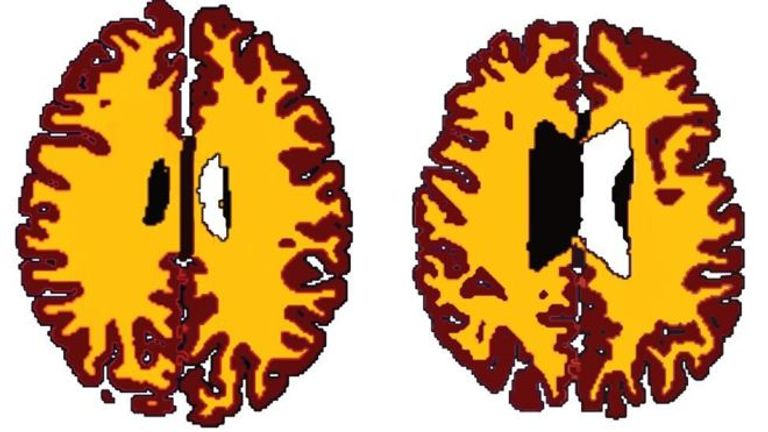

كشفت دراسة لجماعة "كامبريدج" البريطانية، أن جسم الأشخاص الذين يعانون من زيادة الوزن ليس هو فقط الذي يبدو كبيرًا بل إن أدمغتهم أيضًا تبدو أكبر بعشرة أعوام من أدمغة أقرانهم الأقل وزنًا، ما يعني أن السمنة قد تعجل بظهور وتطور شيخوخة الدماغ أكثر من المعتاد.

ولكن فريق الجامعة وجد أن فقدان هذه المادة يتفاقم مع زيادة الوزن، لذلك فإن الشخص البالغ من العمر ٥٠ عامًا ويعاني من زيادة الوزن لديه مخ مثل مخ الشخص النحيف البالغ من العمر ٦٠ عامًا.

وأوضح العلماء أن أدمغة البدناء تفقد بنيتها الأساسية بصور أسرع، ويقولون إن ذلك يؤكد الحاجة لمعرفة المزيد حول كيفية تأثير الوزن الزائد على الدماغ.

ووجدت النتائج التي نشرت في دورية علم أعصاب الشيخوخة، فروقًا مهمة في حجم المادة البيضاء في أدمغة الأشخاص الذين يعانون من زيادة الوزن مقارنة بالأشخاص الأقل وزنًا.

وكانت المادة البيضاء في أدمغة زائدي الوزن أقل بكثير منها عند نظرائهم الأقل وزنًا.

ولم يظهر الفرق بوضوح إلا في منتصف العمر وما بعده، ما يشير إلى أن أدمغتنا قد تكون عرضة للشيخوخة أثناء هذه الفترة.